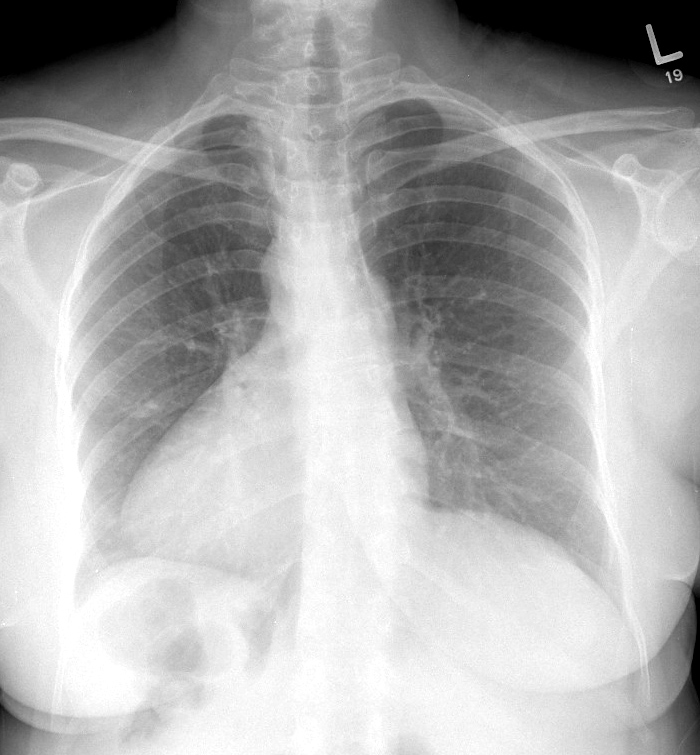

Congenital

Situs Inversus